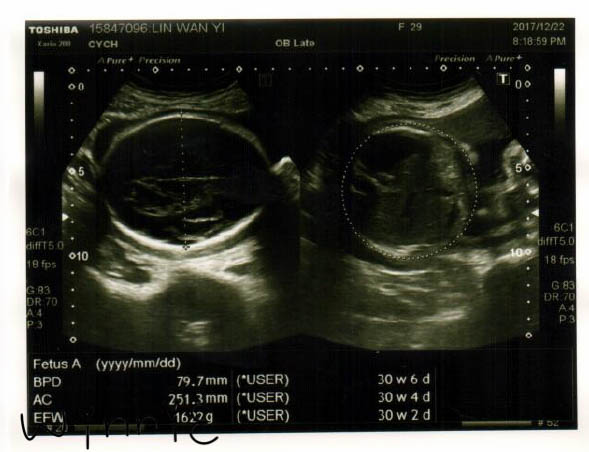

兩週不見,小妞長胖了400g,難怪最近覺得肚子愈來愈沉,愈來愈重啊,都有點快走不動的感覺了,運動稍顯吃力;王醫師說血流很好,心跳很好,整體狀況都不錯,接著就急忙趕去接生了,還好先看完了,護理師在一旁說我們很幸運,不然就要等王醫生接生完回來才能檢查了。

王醫師叮囑由於之前看診過於頻繁,十次的健保剩下兩次了(笑),所以從現在開始不時要開始自費產檢了,這幾個月做了各種檢查也真的是跑了不少次醫院,不過阿爸總說醫院不遠,只要心有不安和擔心就該檢查(真暖心),目前一般時段(早診和下午診)費用是$100,晚診是$150,這次自費檢查費用是$390。